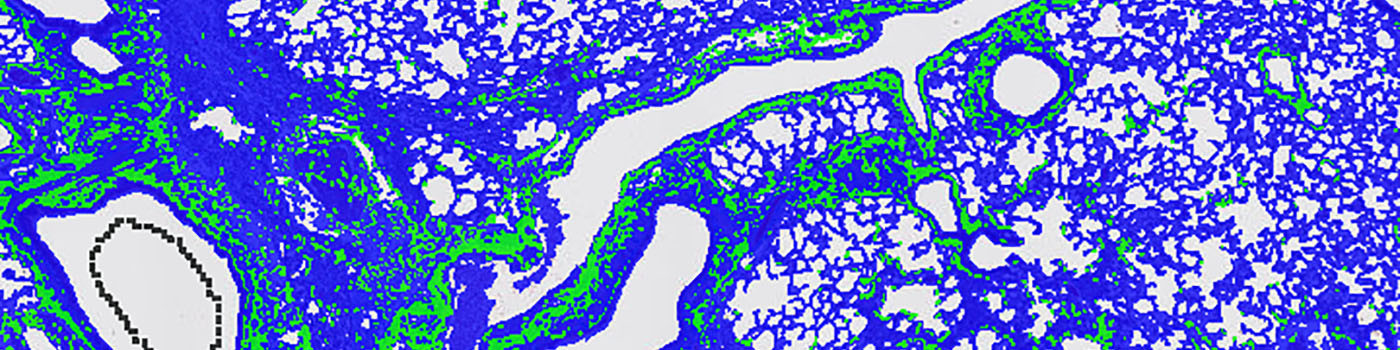

The first image processing step involves a segmentation of the lung tissue from the background. This can be done automatically or manually depending on the complexity and quality of the image. As the collagen is quite distinct from the rest of the tissue, a threshold classifier is applied to a Red-Blue Contrast band. This segments the bluish collagen from the rest of the tissue.